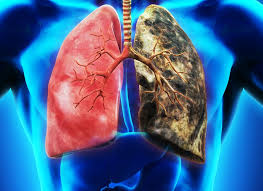

① 흡연

가장 주요한 위험인자입니다. 전체 폐암의 약 80~90%는 흡연과 관련 있으며, 비흡연자에 비해 폐암 발생 위험이 수 배 높습니다.

② 간접흡연

가정이나 직장에서의 간접흡연도 폐암 위험을 높입니다. 장기간 노출될 경우 비흡연자도 높은 발병률을 보입니다.